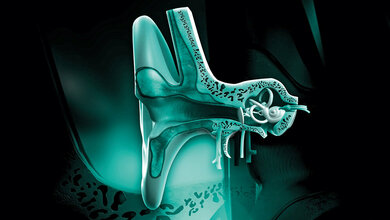

Laut WHO leiden weltweit 466 Millionen Menschen (davon 34 Millionen Kinder) an einer behandlungsbedürftigen Schwerhörigkeit. Ursächlich für die häufigste Form der Schwerhörigkeit sind defekte oder abgestorbene Hörsinneszellen. Bisher ist es nicht möglich, diese Sinneszellen zu reparieren oder wiederherzustellen. Die klinische Versorgung beruht daher auf Hörgeräten bei leicht- bis mittelgradiger Schwerhörigkeit und Cochlea-Implantaten (CI) bei hochgradiger Schwerhörigkeit und Taubheit. Das elektrische Cochlear-Implantat blickt schon auf eine lange Geschichte zurück. Nachdem im Jahr 1950 die erste direkte Stimulation des menschlichen Hörnervs durch Ludenberg erfolgte, entwickelten die Physiker André Djourno und der Otologe Charles Eyriès 1957 das erste funktionierende Cochlea-Implantat. Derzeit werden die CIs weltweit von mehr als einer Million Menschen genutzt. Die Innenohr-Implantate ermöglichen den Betroffenen ein Sprachverstehen in ruhiger Umgebung. Doch Nutzerinnen und Nutzer haben Schwierigkeiten, Sprache bei Hintergrundgeräuschen zu verstehen, den emotionalen Tonfall von Sprache zu interpretieren oder Melodien in Musik zu genießen. Daher bestehe ein großer klinischer Bedarf, das Hören mit CI zu verbessern. Im Fokus der Forschung stehe deshalb das „Hören mit Licht“ mit einem optischen CI, so die Projektverantwortlichen. Dieses verspreche Nutzerinnen und Nutzern, Sprache in geräuschreicher Umgebung deutlich besser zu verstehen und auch Sprachmelodien zu erkennen.

Da Licht räumlich wesentlich besser begrenzt werden kann als elektrische Reize, verspricht die optische Stimulation des Hörnervs die Grenzen der derzeitigen elektrischen CIs zu überwinden. Durch die Kombination eines optischen CI mit einer Gentherapie werde eine fundamentale Verbesserung der Frequenzauflösung erreicht. Dabei werde die Gentherapie genutzt, um einen Licht-aktivierbaren Ionenkanal („molekularer Lichtschalter“) in Spiralganglionneuronen der Cochlea einzuschleusen und diese lichtempfindlich zu machen. Was im Tiermodell bereits erfolgreich umgesetzt wurde, gelte es nun für die Anwendung beim Menschen weiterzuentwickeln.

Bis zum geplanten Start der ersten klinischen Studie im Jahr 2027 bestehe jedoch noch ein erheblicher Forschungsbedarf, so die Projektteilnehmer. So soll mit den Mitteln ein verlustleistungsarmer Chip entwickelt werden, der für das Betreiben der Laserdioden des optischen CIs benötigt wird. Dabei werden die Laserdioden entsprechend der Tonfrequenz aktiviert und das Licht der Dioden über Wellenleiter an die der Tonfrequenz entsprechende Stelle der Hörschnecke geleitet. Das dort ausgekoppelte Licht stimuliert dann die lichtempfindlich gemachten Hörnervenzellen.